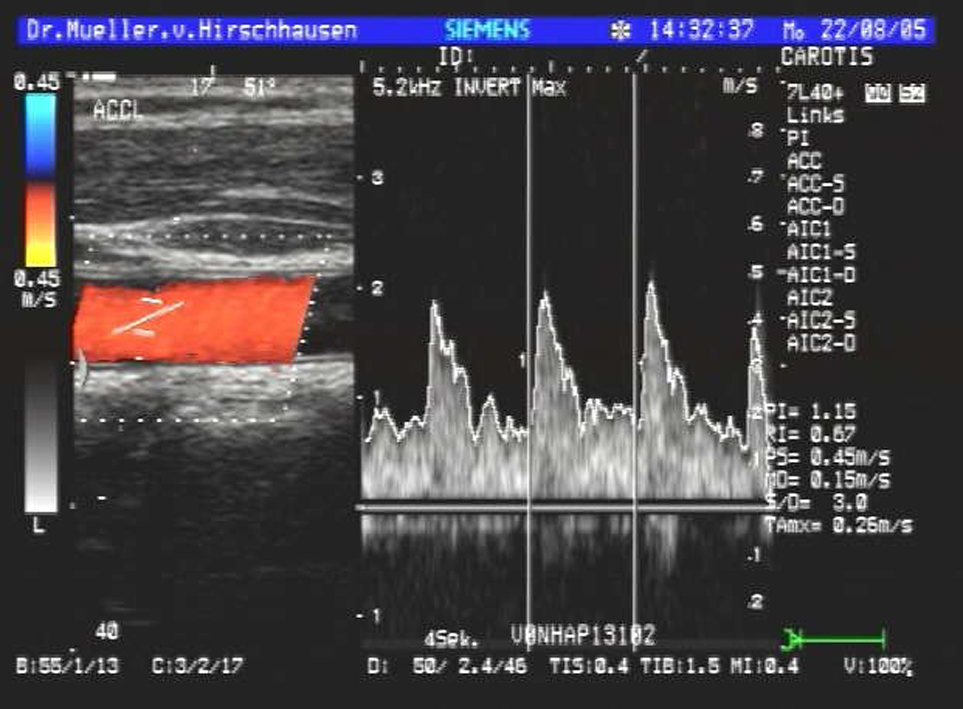

| Halsschlagader | |

Dazu kommen neben dem üblichen schwarz-weiß Bild auch moderne Verfahren zum Einsatz wie Farbdopplersonographie und Kontrastmittelsonographie der Leber.